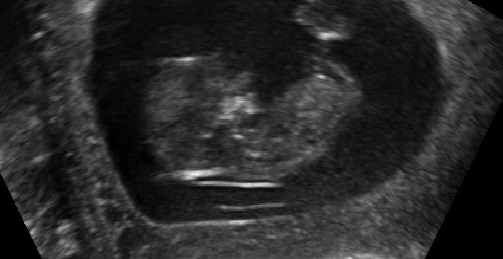

I was 11w5d when I had the scan, although I was measuring 12w1d. I know it's still pretty early, but am wondering if you see anything on these (terrible quality) scan pics! Attachment 23572Attachment 23571Attachment 23573Attachment 23574Attachment 23575